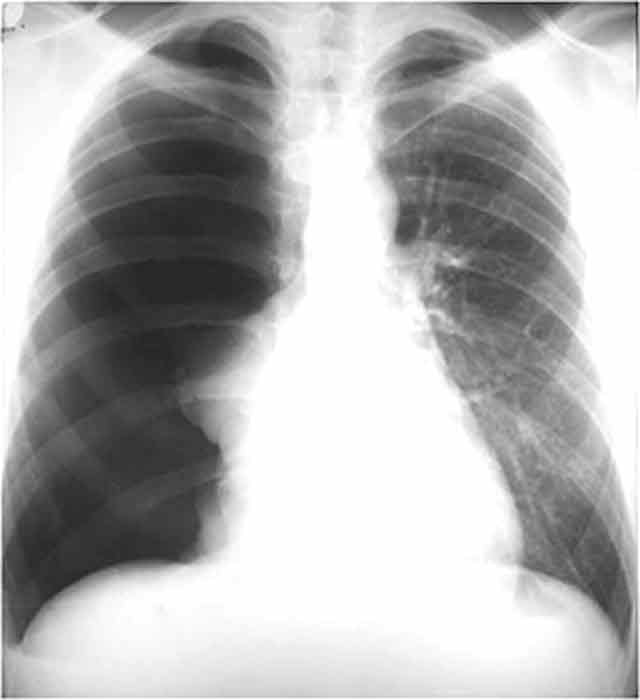

What is the pathology which is seen in this image?

Bronchiectasis

What is the classification of this pathology?

inflammatory and degenerative

The pathology in this image is seen radiographically as

Diluted and fluid filled bronchioles